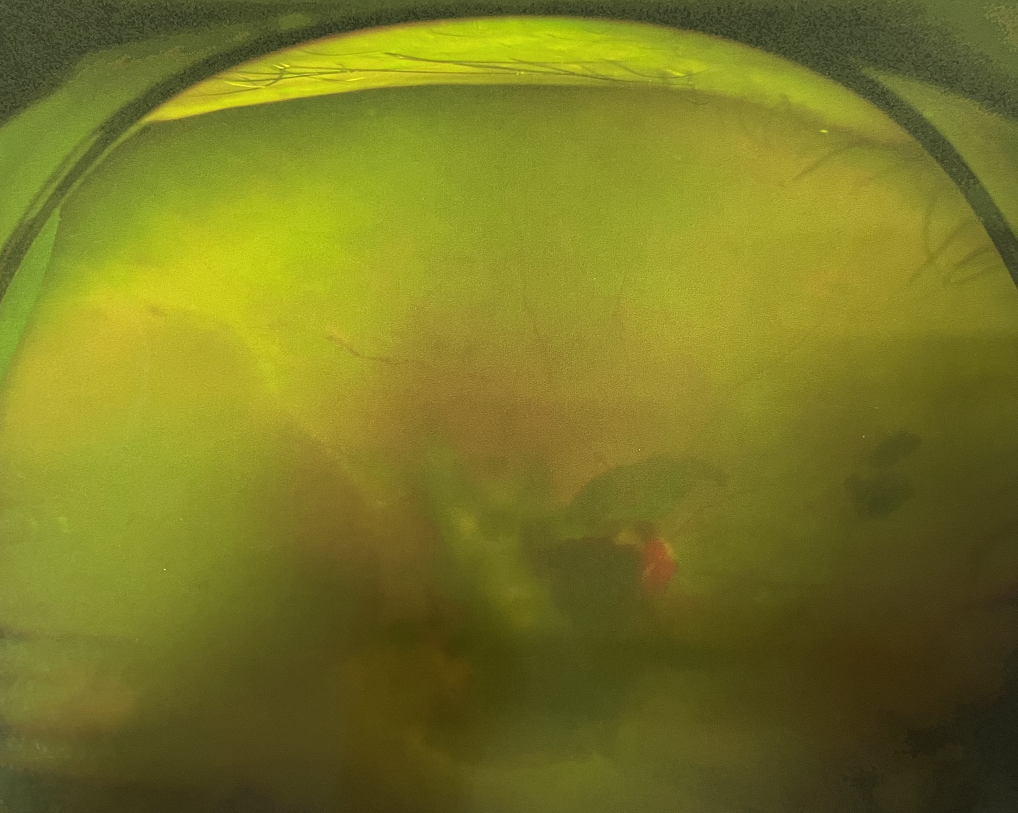

四十多歲的王女士,患高血壓病及Ⅱ型糖尿病多年,一直靠藥物控制血壓和血糖。去年,王女士右眼看手機(jī)時(shí)感覺視物不清,總感覺眼前有一層霧,視力也逐漸下降,于是來廈門大學(xué)附屬?gòu)B門眼科中心就診。

眼底病??茝埿』⑨t(yī)生檢查后,診斷王女士為“雙眼玻璃體積血、雙眼糖尿病視網(wǎng)膜病變V期”。(V期即5期,纖維增生期,出現(xiàn)纖維膜,可伴視網(wǎng)膜前出血或玻璃體出血。)

張小虎醫(yī)生為王女士進(jìn)行右眼玻璃體腔注藥術(shù),3天后進(jìn)行右眼23G玻璃體切割術(shù)后視力有所提升。

4個(gè)月后王女士來院取硅油,取油后視力恢復(fù)到0.6。“當(dāng)時(shí)來的時(shí)候真的只能看到模糊的影子,特別害怕覺得完了,想說眼睛估計(jì)要瞎了,沒想到手術(shù)后視力竟然提升了,現(xiàn)在也看得比較清楚了。”王女士說到。

張小虎醫(yī)生表示,糖網(wǎng)病進(jìn)展到嚴(yán)重增殖期帶來的視力損傷往往是極其嚴(yán)重的,目前王女士右眼從術(shù)前0.02恢復(fù)到術(shù)后0.6,已屬十分難得。

右眼術(shù)前